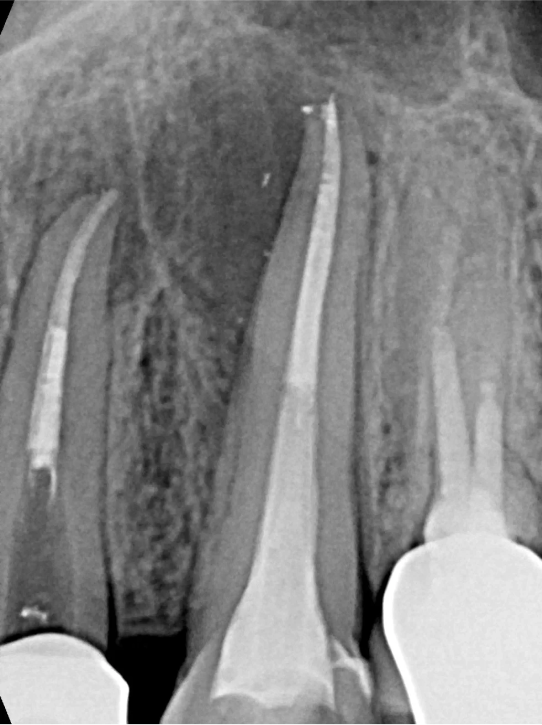

Po zakończonym leczeniu kanałowym, wykonujemy kontrolne zdjęcie RTG. Pozwala ono na natychmiastową ocenę jakości wypełnienia kanałów korzeniowych i potwierdzenie skuteczności przeprowadzonego zabiegu. Dla nas leczenie kanałowe Opole to synonim precyzji i pewności.

Na podstawie zdjęcia rentgenowskiego określa się kształt i długość kanału bądź za pomocą specjalnego urządzenia mierzy się jego długość. Potem lekarz otwiera wejścia do kanału, chroniąc ząb koferdamem, czyli specjalną gumą, zapewniającą sterylność oraz chroniącą przed środkami chemicznymi służącymi do oczyszcza-nia kanału. Używa się do tego zarówno specjalistycznego sprzętu, jak i nowo-czesnych mikroskopów, pozwalających na uzyskanie dokładnego obrazu leczone-go zęba. Ostatnią czynnością jest wypełnienie materiałem światłoutwardzal-nym i zabezpieczenie zęba przed dostaniem się i rozwojem bakterii mogących wywołać wtórny stan zapalny.

Przed rozpoczęciem leczenia kanałowego kluczowa jest dokładna diagnostyka. Zazwyczaj wykonujemy kontrolne zdjęcia RTG, a czasem nawet kilka, aby precyzyjnie ocenić stan zęba i otaczających go tkanek. W bardziej skomplikowanych przypadkach możemy zlecić wykonanie tomografii komputerowej (CBCT) dla uzyskania trójwymiarowego obrazu.

Nasza diagnostyka to nie tylko cyfrowe zdjęcia RVG (radiowizjografia), które ograniczają dawkę promieniowania i dają natychmiastowy obraz. W skomplikowanych przypadkach kierujemy pacjentów na tomografię komputerową CBCT, która daje trójwymiarowy obraz struktur zębowych i kostnych, co jest nieocenione przy planowaniu trudnego leczenia kanałowego lub ponownego leczenia endodontycznego.